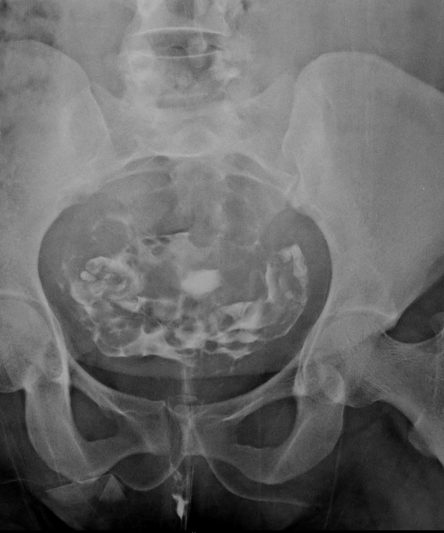

Microskan with Ultra high frequency can take the Lateral Lumbar Spine image of a 90 kg Patient with the correct image receptor